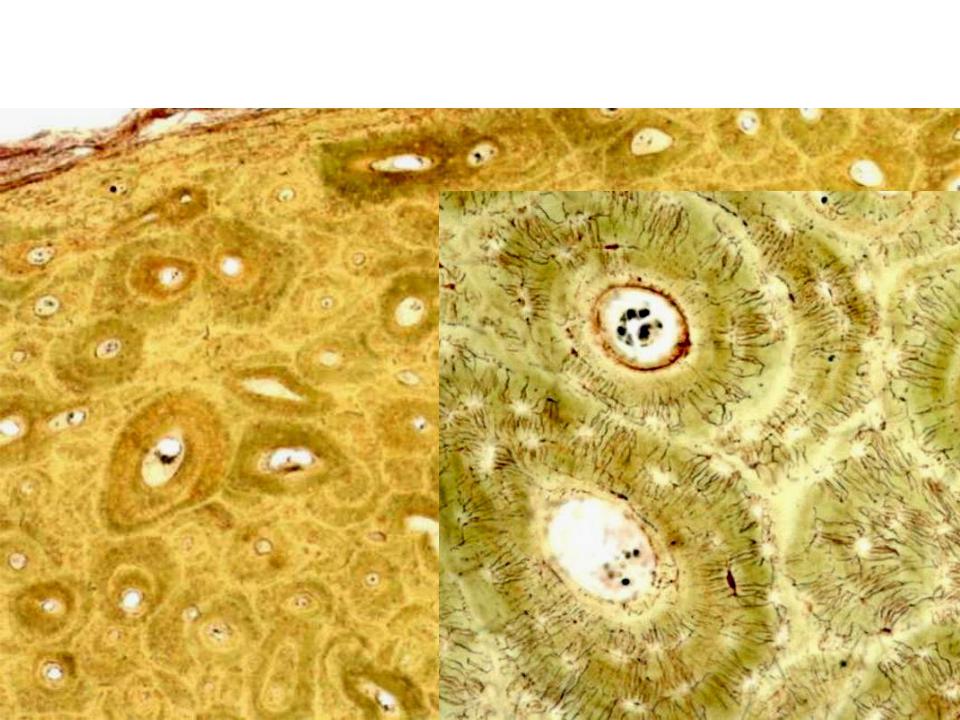

Структура грубоволокнистой костной ткани: наглядные примеры